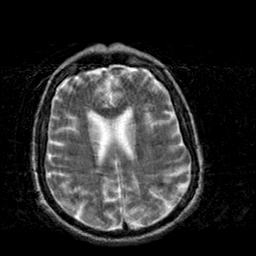

Creutzfeld-Jakob disease: T2-weighted MR -- Slice #15

[Home][Help][Clinical] Slice 15